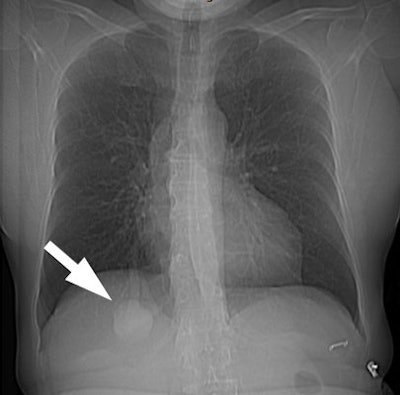

On plain films, AVM's generally appear as a solitary or multiple

pulmonary nodules. Classically one should be able to identify the

enlarged vessel entering the lesion. The lesion will be noted to

change size with inspiration and expiration, or supine versus

erect films.

| The patient shown below had a

large right lower lobe AVM (white arrow). Note the large

vessel extending to the lesion. |